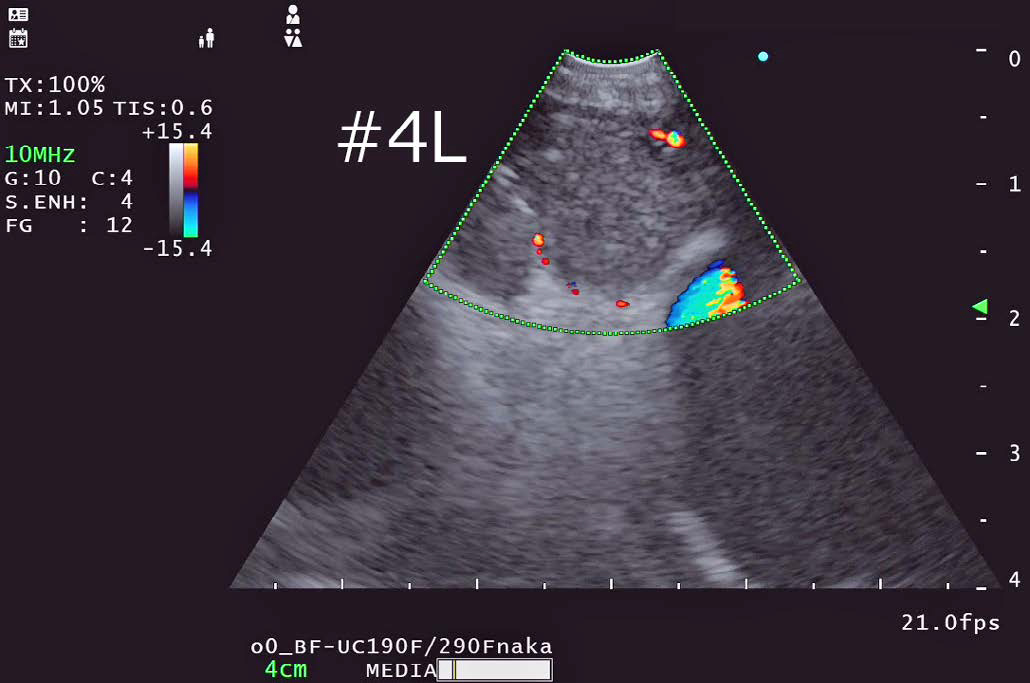

FLOW モード

•  EU-ME2と同様に右記のドプラーモードが使用可能である。

基本となるBモードの解像度が向上している影響か、色のにじみが少なくメリハリの利いたドップラー画像になっていると感じた。

当院ではTBNA施行時には血管からのはみ出しを抑えて血流表示するハイフローを基本的に使用し、穿刺前に血管介在を確認している。

• ハイフロー:血流の向きと強度をカラー表示

• ハイフロー